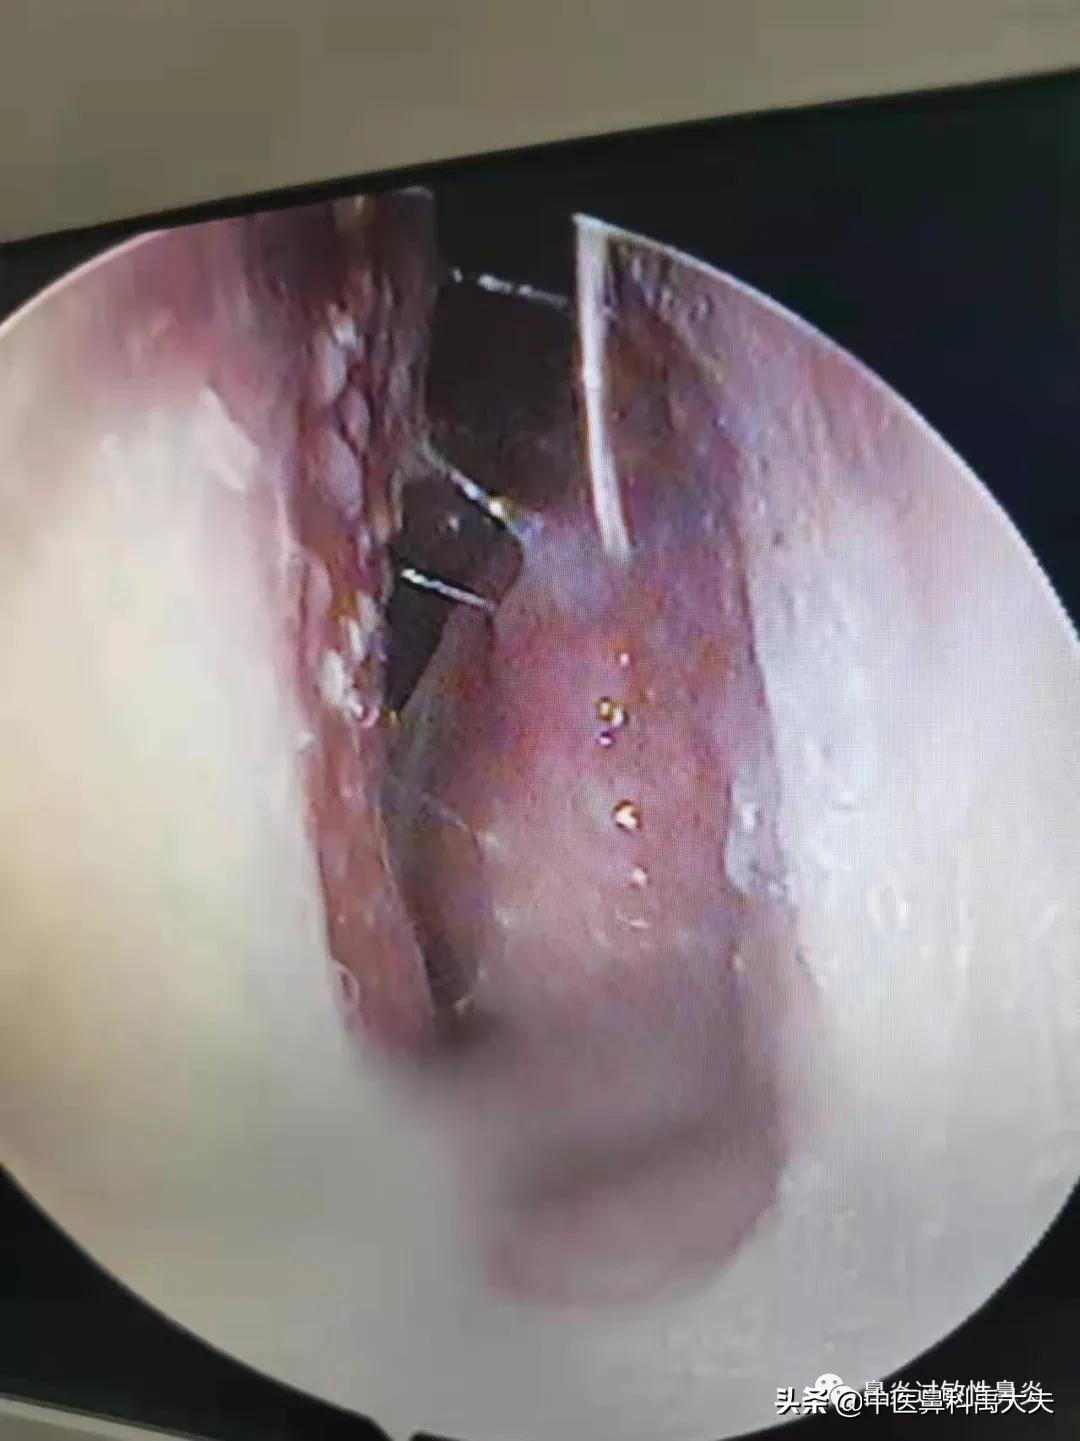

左侧鼻腔

鼻腔内窥镜检查可见下、中鼻甲肥大,鼻腔黏膜苍白,鼻中隔轻度偏曲,鼻中隔和鼻甲上伴有凸起样白色颗粒物;舌苔白腻水滑,伴有轻度口干口苦。具体舌苔图和鼻腔内镜图如下:

右侧鼻腔